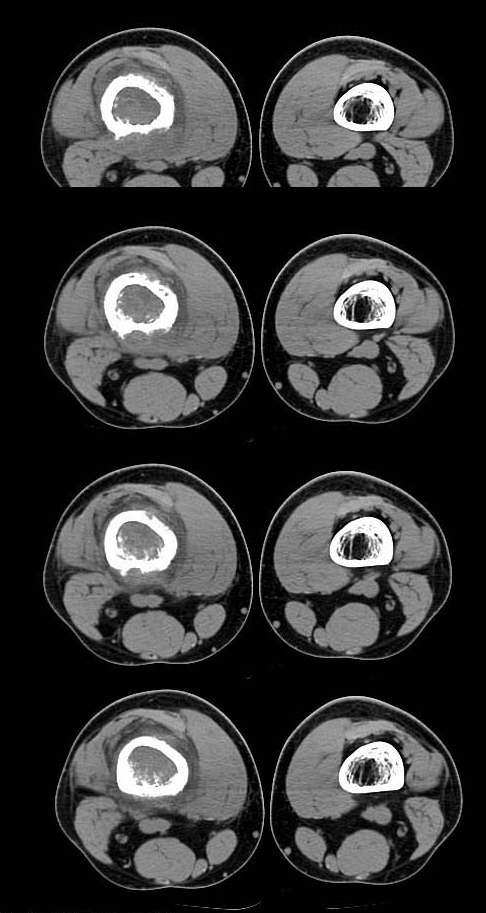

20岁,男,右股骨下端疼痛一个月,无发热,白细胞正常,皮肤不红,肿胀,触痛。

右股骨下端很长范围内的髓腔扩大,骨小梁破坏消失,皮质亦呈融骨性破坏,周围脂肪层次紊乱,肌肉受累及密度减低。考虑为:恶性骨肿瘤。请专家们分析骨肉瘤及尤文氏肉瘤的ct征象。

长骨ct见的较少,该病例股骨下端表现为边缘模糊的溶骨性破坏,伴有费用性脱钙,髓腔密度增高,呈毛玻璃样改变,病变周围软组织肿胀,脂肪间隙模糊,无骨膜反应,应密切结合临床,考虑骨纤维肉瘤或慢性骨脓肿。期待结果。

此病例基本可定是恶性骨肿瘤:髓腔内长范围肿块、皮质不规则破坏、软块及软组织浸润、瘤骨及不规则骨膜反应等。可以肯定地除外炎性病变和骨纤。

结合临床还是将尤文氏肉瘤放在前面,骨肉瘤不排除。纤维肉瘤及恶纤组多见老年人,不放在首要诊断范围内。